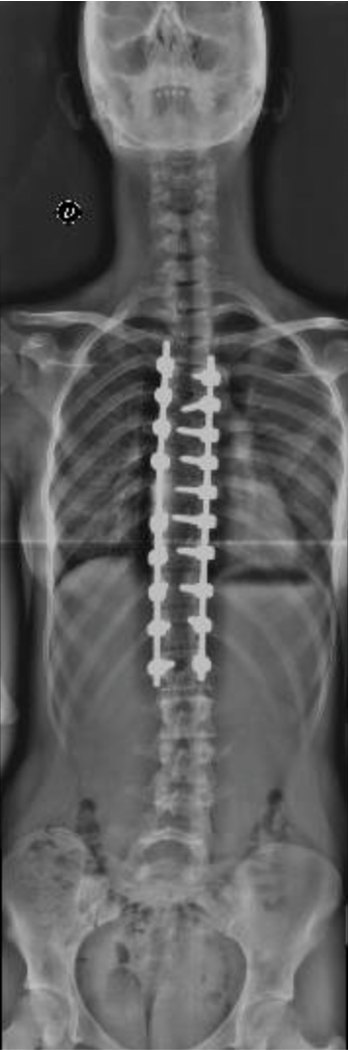

Morena

Inicio del tratamiento:

2018

Edad de la paciente:

10 años

Patología:

Escoliosis Idiopática del Adolescente.

Tratamiento: Uso de un corsé, y ejercicios indicados para prevenir la progresión de la curvatura. Al año: la escoliosis y el valor angular empeoraron significativamente En la primavera del 2020, plena pandemia, se llevó a cabo la corrección quirúrgica. Hoy, Morena ha logrado retomar sus actividades y actualmente juega al hockey. Su evolución refleja cómo, a pesar de las dificultades, se puede avanzar en el tratamiento de la escoliosis.